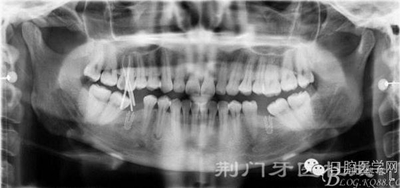

X線片

檢查:16齲壞穿髓,探(-)叩(+++),無(wú)松動(dòng),36 46 缺失,37 47 近中傾斜嚴(yán)重,44畸形中央尖牙體變色,叩(+),溫度測(cè)試無(wú)反應(yīng) ,18 28 38 48 萌出牙體偏頰

1:16 根尖炎

2:44根尖炎

3:牙列缺損